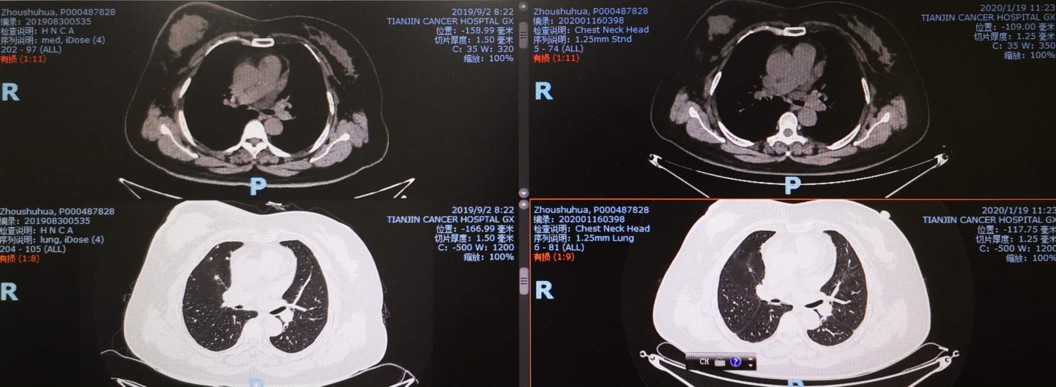

影像学检查:2019年9月CT发现双肺多发转移。

2019-9-2 2020-1-19